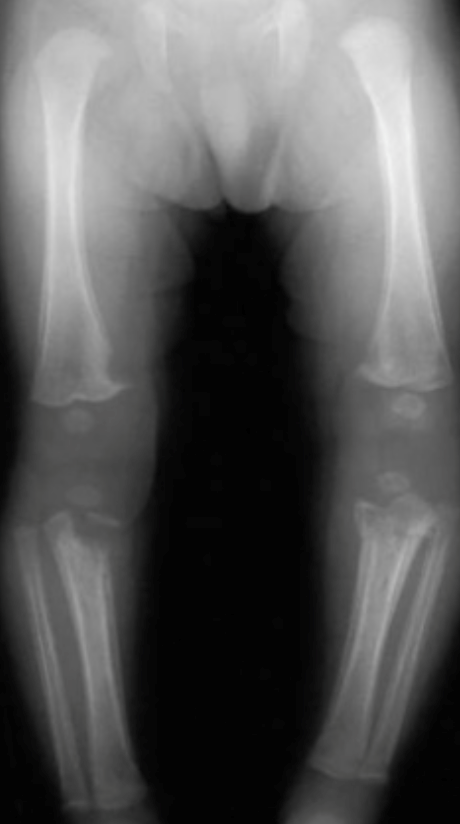

A incidência de sífilis infelizmente ainda é comum nos dias de hoje. A transmissão vertical da sífilis da gestante infectada para o feto pode atingir até 100% dos casos das mães não tratadas nas fases primária e secundária da doença. O germe se dissemina via hematogênica e o Treponema pallidum pode ser encontrado na medula óssea precocemente, menos de dois dias após o início da infecção. A infecção também pode ocorrer no canal do parto caso tenha feridas locais. Mais de 50% dos casos de sífilis congênita atingem os ossos. Os patógenos tendem a se localizar nas metáfises e diáfises dos ossos, poupando as articulações. Os ossos mais comumente acometidos são a tíbia, o úmero e o fêmur (FIGURA 1).

FIGURA 1. Acometimento múltiplo de ossos, principalmente nas diáfises e metáfises.